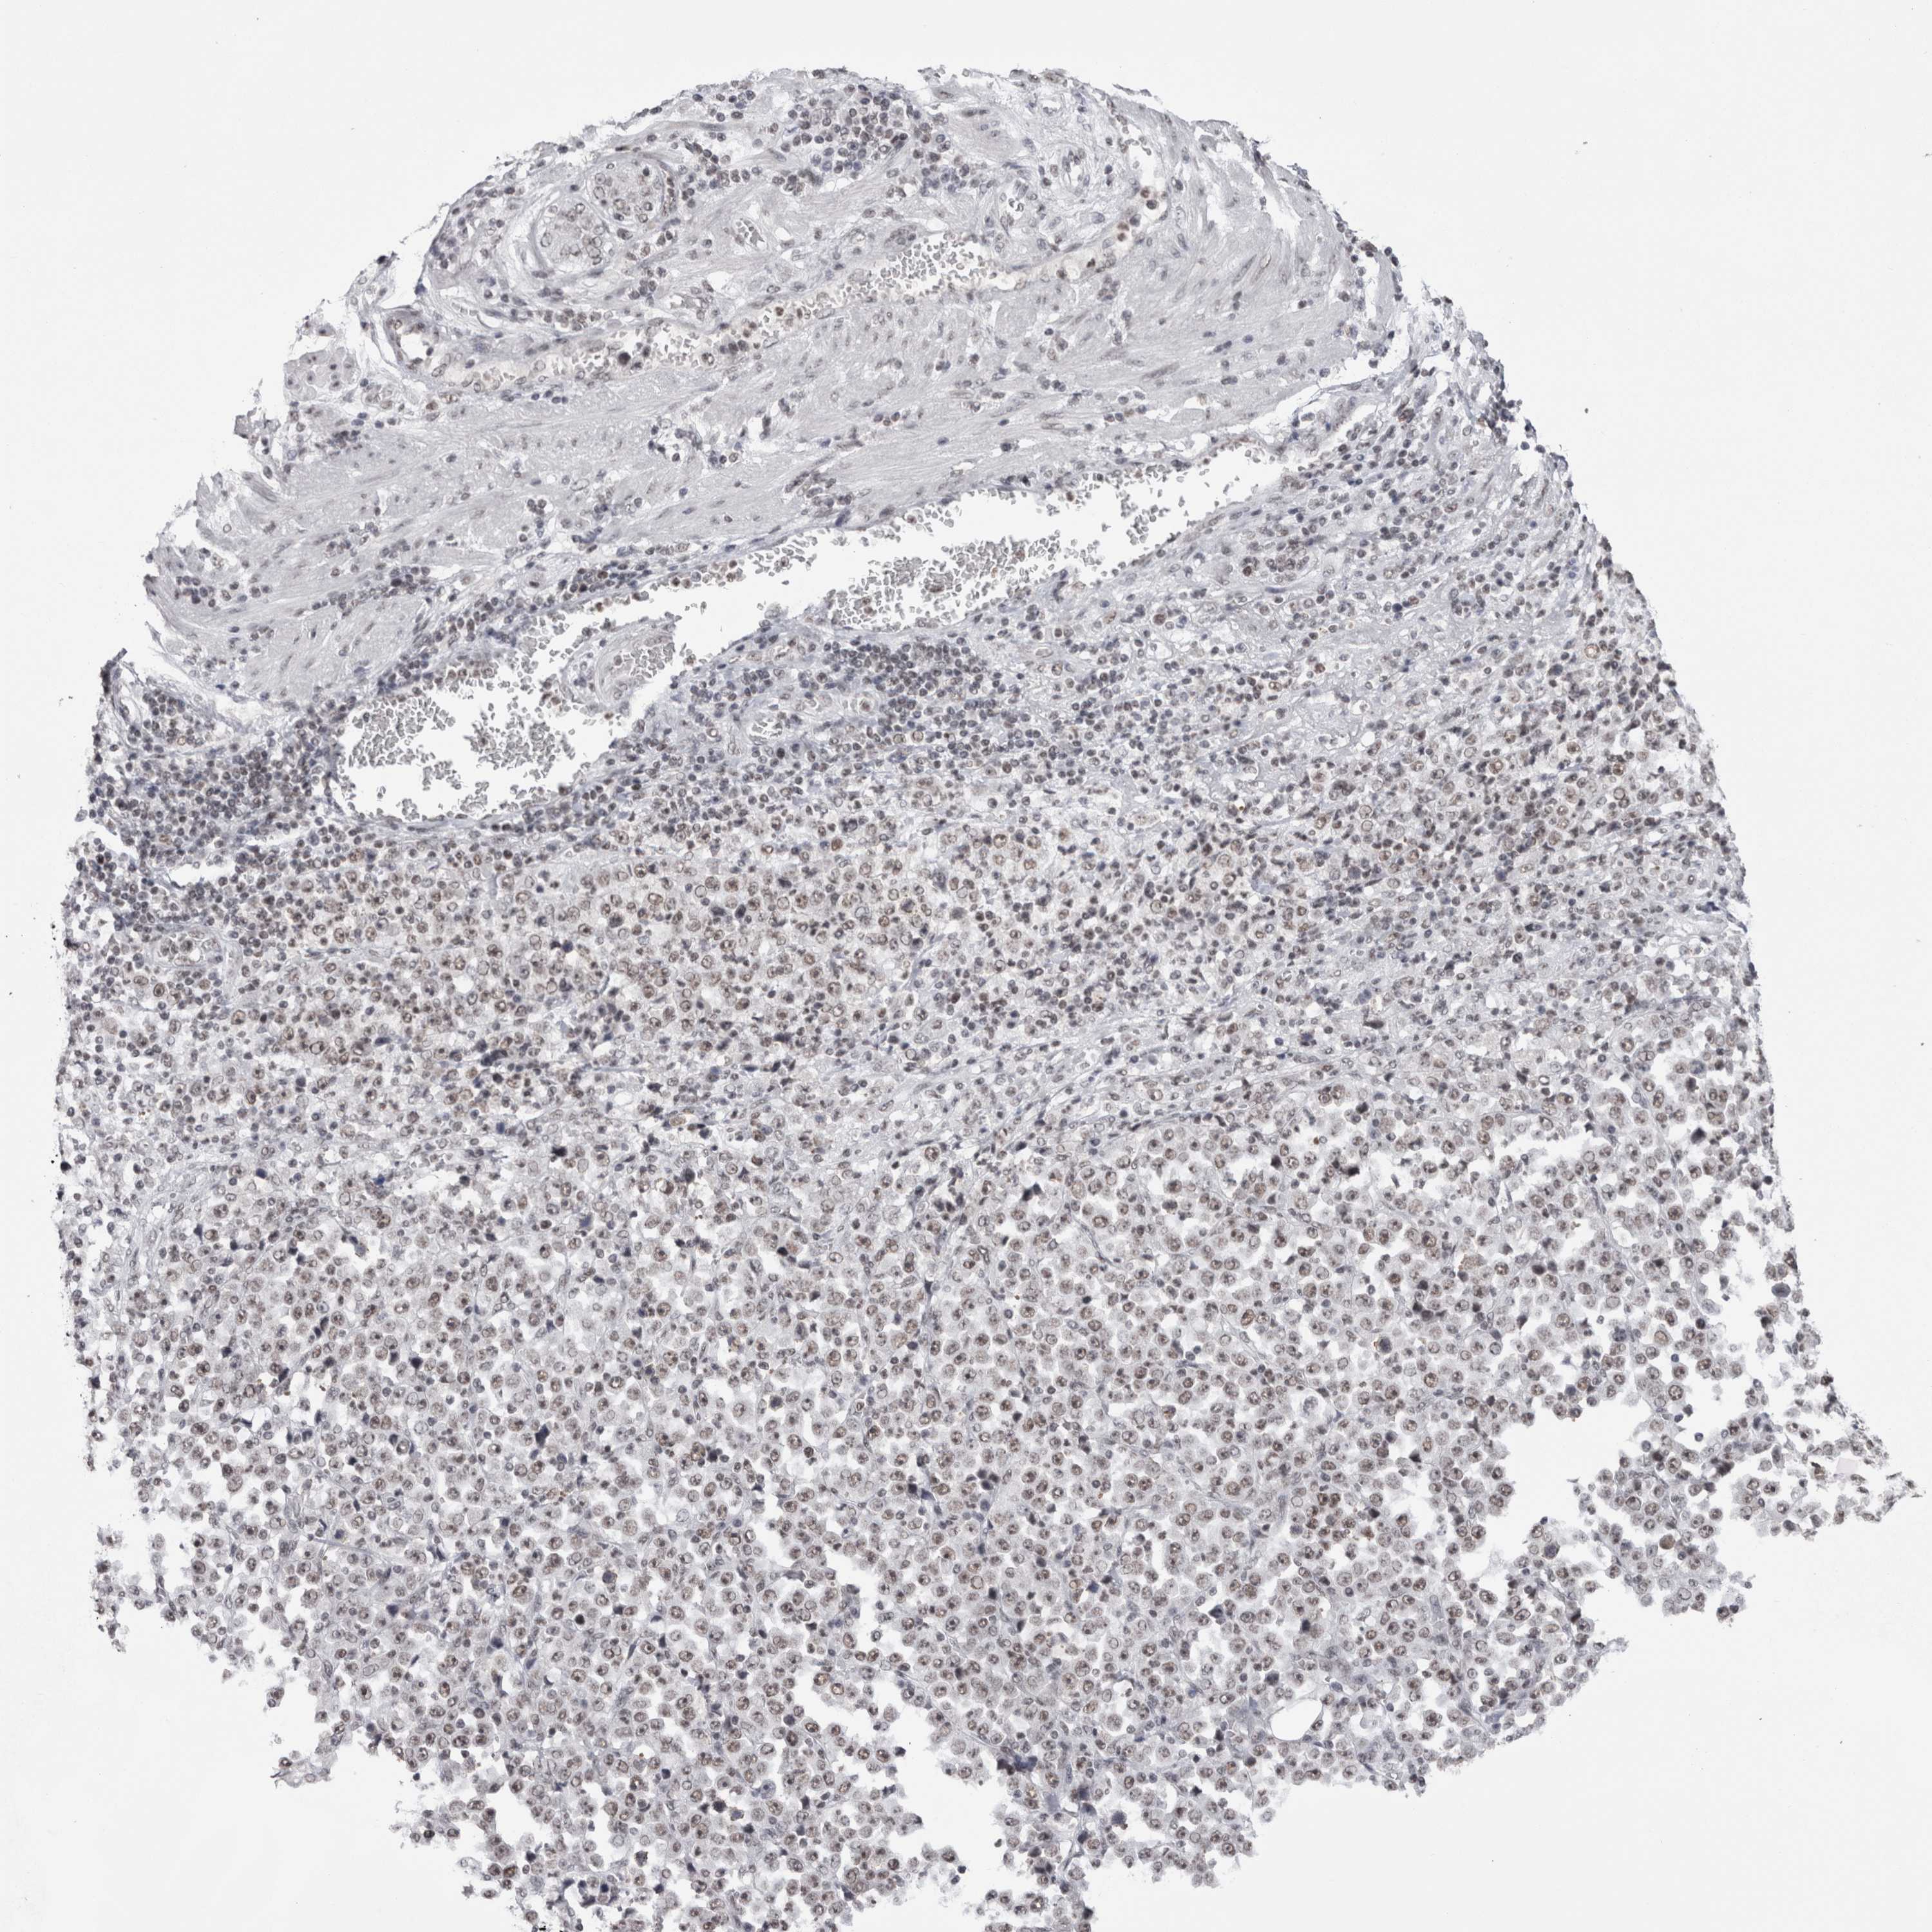

STOMACH CANCER - Protein expressioni

A mouse-over function shows sample information and annotation data. Click on an image to view it in a full screen mode. Samples can be filtered based on level of antibody staining by selecting one or several of the following categories: high, medium, low and not detected. The assay and annotation is described here.

Note that samples used for immunohistochemistry by the Human Protein Atlas do not correspond to samples in the TCGA dataset.

Antibody stainingi

Antibody staining in the annotated cell types in the current human tissue is reported as not detected, low, medium, or high, based on conventional immunohistochemistry profiling in selected tissues. This score is based on the combination of the staining intensity and fraction of stained cells.

Each image is clickable and will lead to virtual microscopy that enables deeper exploration of all samples and also displays staining intensity scores, fraction scores and subcellular localization as well as patient and tissue information for each sample.

Antibody CAB025404

Staining

High

Medium

Low

Not detected

Intensity

Strong

Moderate

Weak

Negative

Quantity

>75%

75%-25%

<25%

None

Location

Nuclear

Cytoplasmic/membranous

Cytoplasmic/membranous,nuclear

Adenocarcinoma, NOS